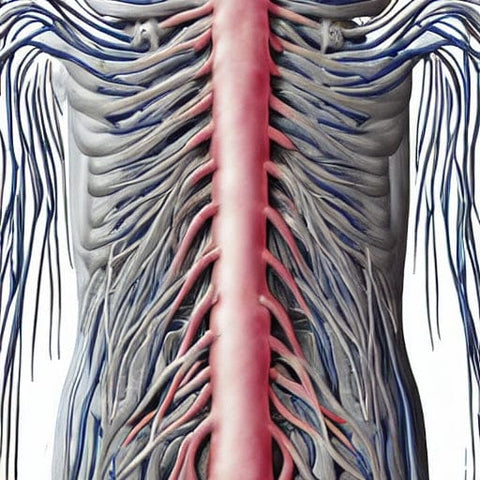

Nervous system

When exposed to EMP, the nervous system is one of the organs that is most susceptible to damage. The power density and frequency of the EMP both have a role in determining the extent of the damage that may be caused by the phenomenon. A number of nations are working to perfect the technology necessary to weaponize EMPs.

In this investigation, an EMP was used on a rat model in order to evaluate the effects that it had on the central nervous system. The effects of electromagnetic pulse (EMP) on learning and memory impairment were investigated using this model.

The electromagnetic pulse was generated by the application of a 400 kV/m electric field for a total of 200 pulses. The Morris water maze was used to assess a participant's learning and memory capacities after 24 hours had passed.

The EMP group's hippocampal neurons had an increased number of dead cells that were labeled with PI. It was also noticed that synaptic clefts were blurred, and secondary lysosomes were present. In addition to this, a considerably greater number of neurons with strongly stained nuclei were seen in the dentate gyrus region of the EMP group.

There is a process called ferroptosis that is known to be responsible for causing damage to the hippocampus. On the other hand, it is not quite obvious how the mechanism operates. It is hypothesized that a physical anomaly like this might result in the death of cells. Therefore, blocking ferroptosis could be a useful treatment strategy.

Downregulation of the GSH/GPX4 axis is another component that may be involved in EMP-induced neuronal injury. This factor is one of many that may be involved. Phospholipid hydroperoxides may be detoxicated thanks to these enzymes. It is possible that a major mechanism to boost neurogenesis is an increase in H3 acetylation that is HDAC2-dependent.

The question of how long the neuronal damage might persist is an important one. Following exposure to an EMP, there is a change in the permeability of the blood-brain barrier. In addition, this disturbance has the potential to result in the creation of reactive nitrogen species.

Previous research has revealed that the cellular alterations that take place after exposure to an EMP might have an effect on learning and memory. As a result, it is necessary to locate efficient medical treatment methods in order to repair the harm.